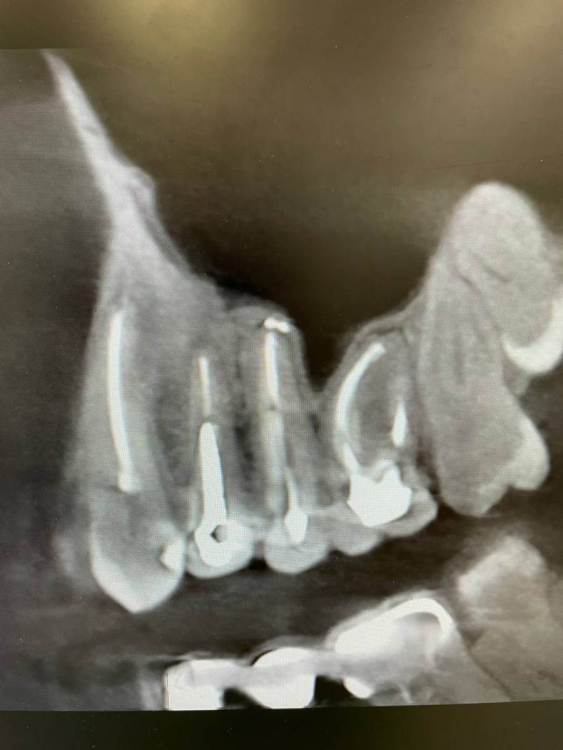

1586Doc Опубликовано 8 апреля, 2022 Автор Поделиться Опубликовано 8 апреля, 2022 (изменено) ресто премоляров эндо 23.24.25.26(ретрит). и контроль спустя 8 месяцев. Изменено 8 апреля, 2022 пользователем 1586Doc 4 1 Ссылка на комментарий